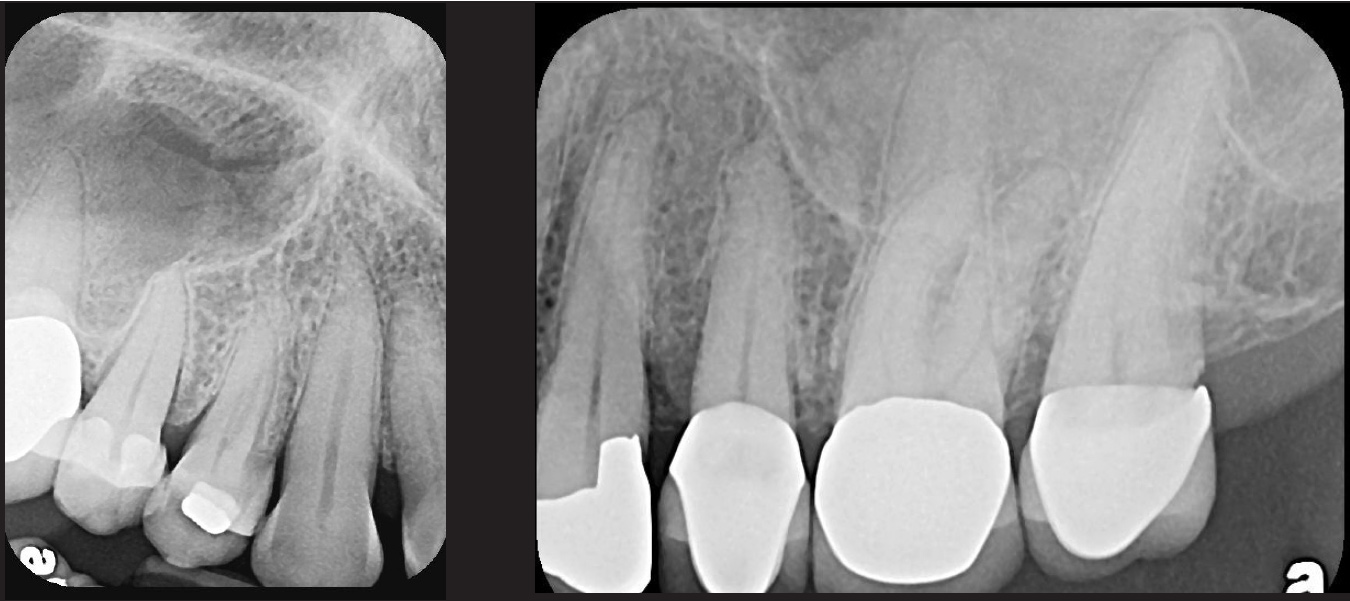

PSP sensor technology offers many advantages to the clinician in patient retention and workflow. The most important consideration is patient comfort and cooperation. PSP sensors are wafer-thin and flexible to allow placement in positions to capture third molar images without gagging or pain. The larger surface area of the most popular no. 2 size PSP sensor allows images of more dental anatomy (Figure 3); therefore, fewer exposures are necessary to create a full-mouth radiographic series. Their flexibility allows placement around tori and exostoses.1,9-12 The bite blocks, stabilizers, BW tabs, and positioning rings that were used for film radiographs will easily accommodate PSP sensor placement.

Some representative radiographic PSP images are exhibited here for demonstration of the anatomy and pathology that can be visualized with this technology. Many of these images would not have been possible if HW technology were used (Figure 3 through Figure 8).

As displayed here, the 2D radiographic images in Figure 3 through Figure 8 can alert the clinician to the need for a further 3D CBCT analysis to properly ascertain the anatomy and extent of the pathology that is initially visible in the intraoral radiographs. Proper treatment or referral to the appropriate specialty practice can follow.5,6 No. 2 PSP radiographs, when used in a conventional full-mouth series of radiographs on a patient with a relatively complete dentition, will routinely allow visualization of the anatomy of third molars, mandibular canal, maxillary sinuses, full dental root morphology, and bone anatomy beyond the apices2,16,17 (Figure 9 and Figure 10).

Fig 3. Two PSP PA radiographs of mandibular teeth showing: left, the initial view

of molar area and suspected pathology surrounding impacted tooth No. 32; center,

subsequently exposed PA radiograph, placed more distally, demonstrates extent

of large cyst as well as entire tooth and root No. 32. Proper alert as to presence

of suspected cyst and appropriate referral for 3D CBCT study and surgical

enucleation was given to the patient. Right: Same radiograph as on the left, but

with lighter superimposed outline of the area that would be visible using an HW

sensor rather than a PSP sensor. The small area of pathology is likely obscured

because it is visually overlaid by the root of tooth No. 31. Neglect of this significant

pathology may have resulted.

Figure 3